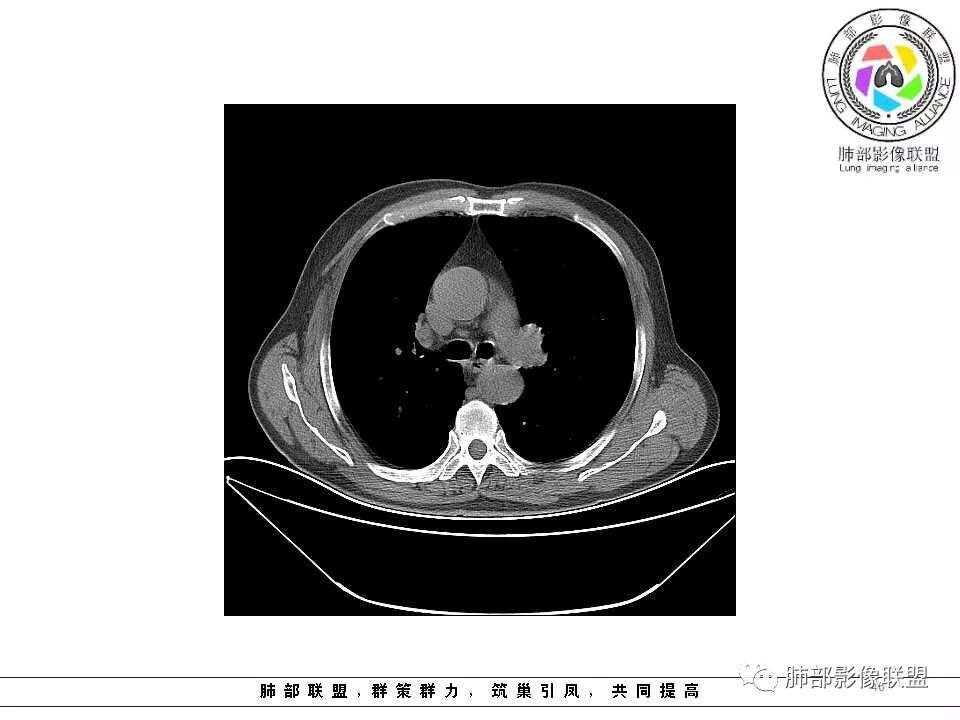

纵隔窗上似乎结节内可见点状高密度影,同时没有明显肿大淋巴结

左肺上叶光滑结节影 似乎与支气管没有关系  ,给的纵隔窗病灶中心似乎点状钙化  病灶旁有更小结节,与上一年片比较 结节增大明显  考虑恶性 类癌可能

肺气肿背景,2016年左肺上叶上舌段见微结节,2017年5月左肺结节增大,密度均匀,边缘光滑锐利,与邻近血管关系密切,血管贴壁走行,外侧见尖状突起,下舌段片状影,沿着支气管走行,内有粘液栓,考虑鳞癌,鉴别小细胞肺癌。

肺气肿背景,2016年左肺上叶上舌段见微结节,一年后左肺结节增大,密度均匀,边缘光滑、膨隆,似见小分叶,下舌段片状影,沿着支气管走行,内,老年患者,咯血1月。考虑恶性病变并阻塞性肺炎,鳞癌?注意鉴别结核。

南大标注,这几个确实结节没有阻塞支气管,感觉是在血管分叉地方。

@南边 关键是上面这几个结节有的密度度,有的密度低。与下面堵塞支气管的结节样改变是否不是一回事,

@南边 我觉得最关键的是两个问题,一是腔内堵塞这个结节的纵隔窗看不到,所以到底是不是结节样肿物不明确,第二个就是没有增强,这个腔内病变与周围结节的强化性质是否一致,强化程度及强化曲线如何?